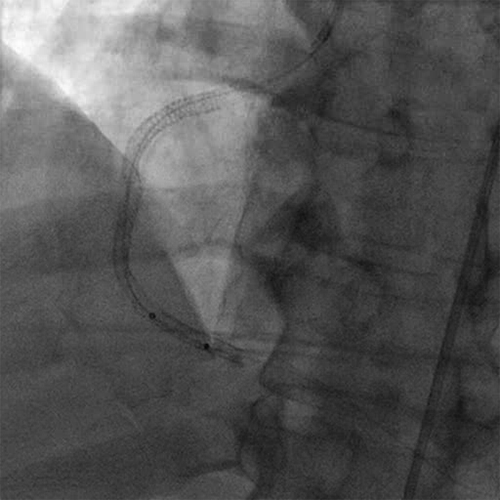

Diagnostic Angiogram

• Initial angiogram showed TIMI 0 flow

• Initial angiogram showed thrombus grade of 5

• The RCA was occluded in the mid vessel (Cine 1: Occluded RCA Acute Stent Thrombosis)